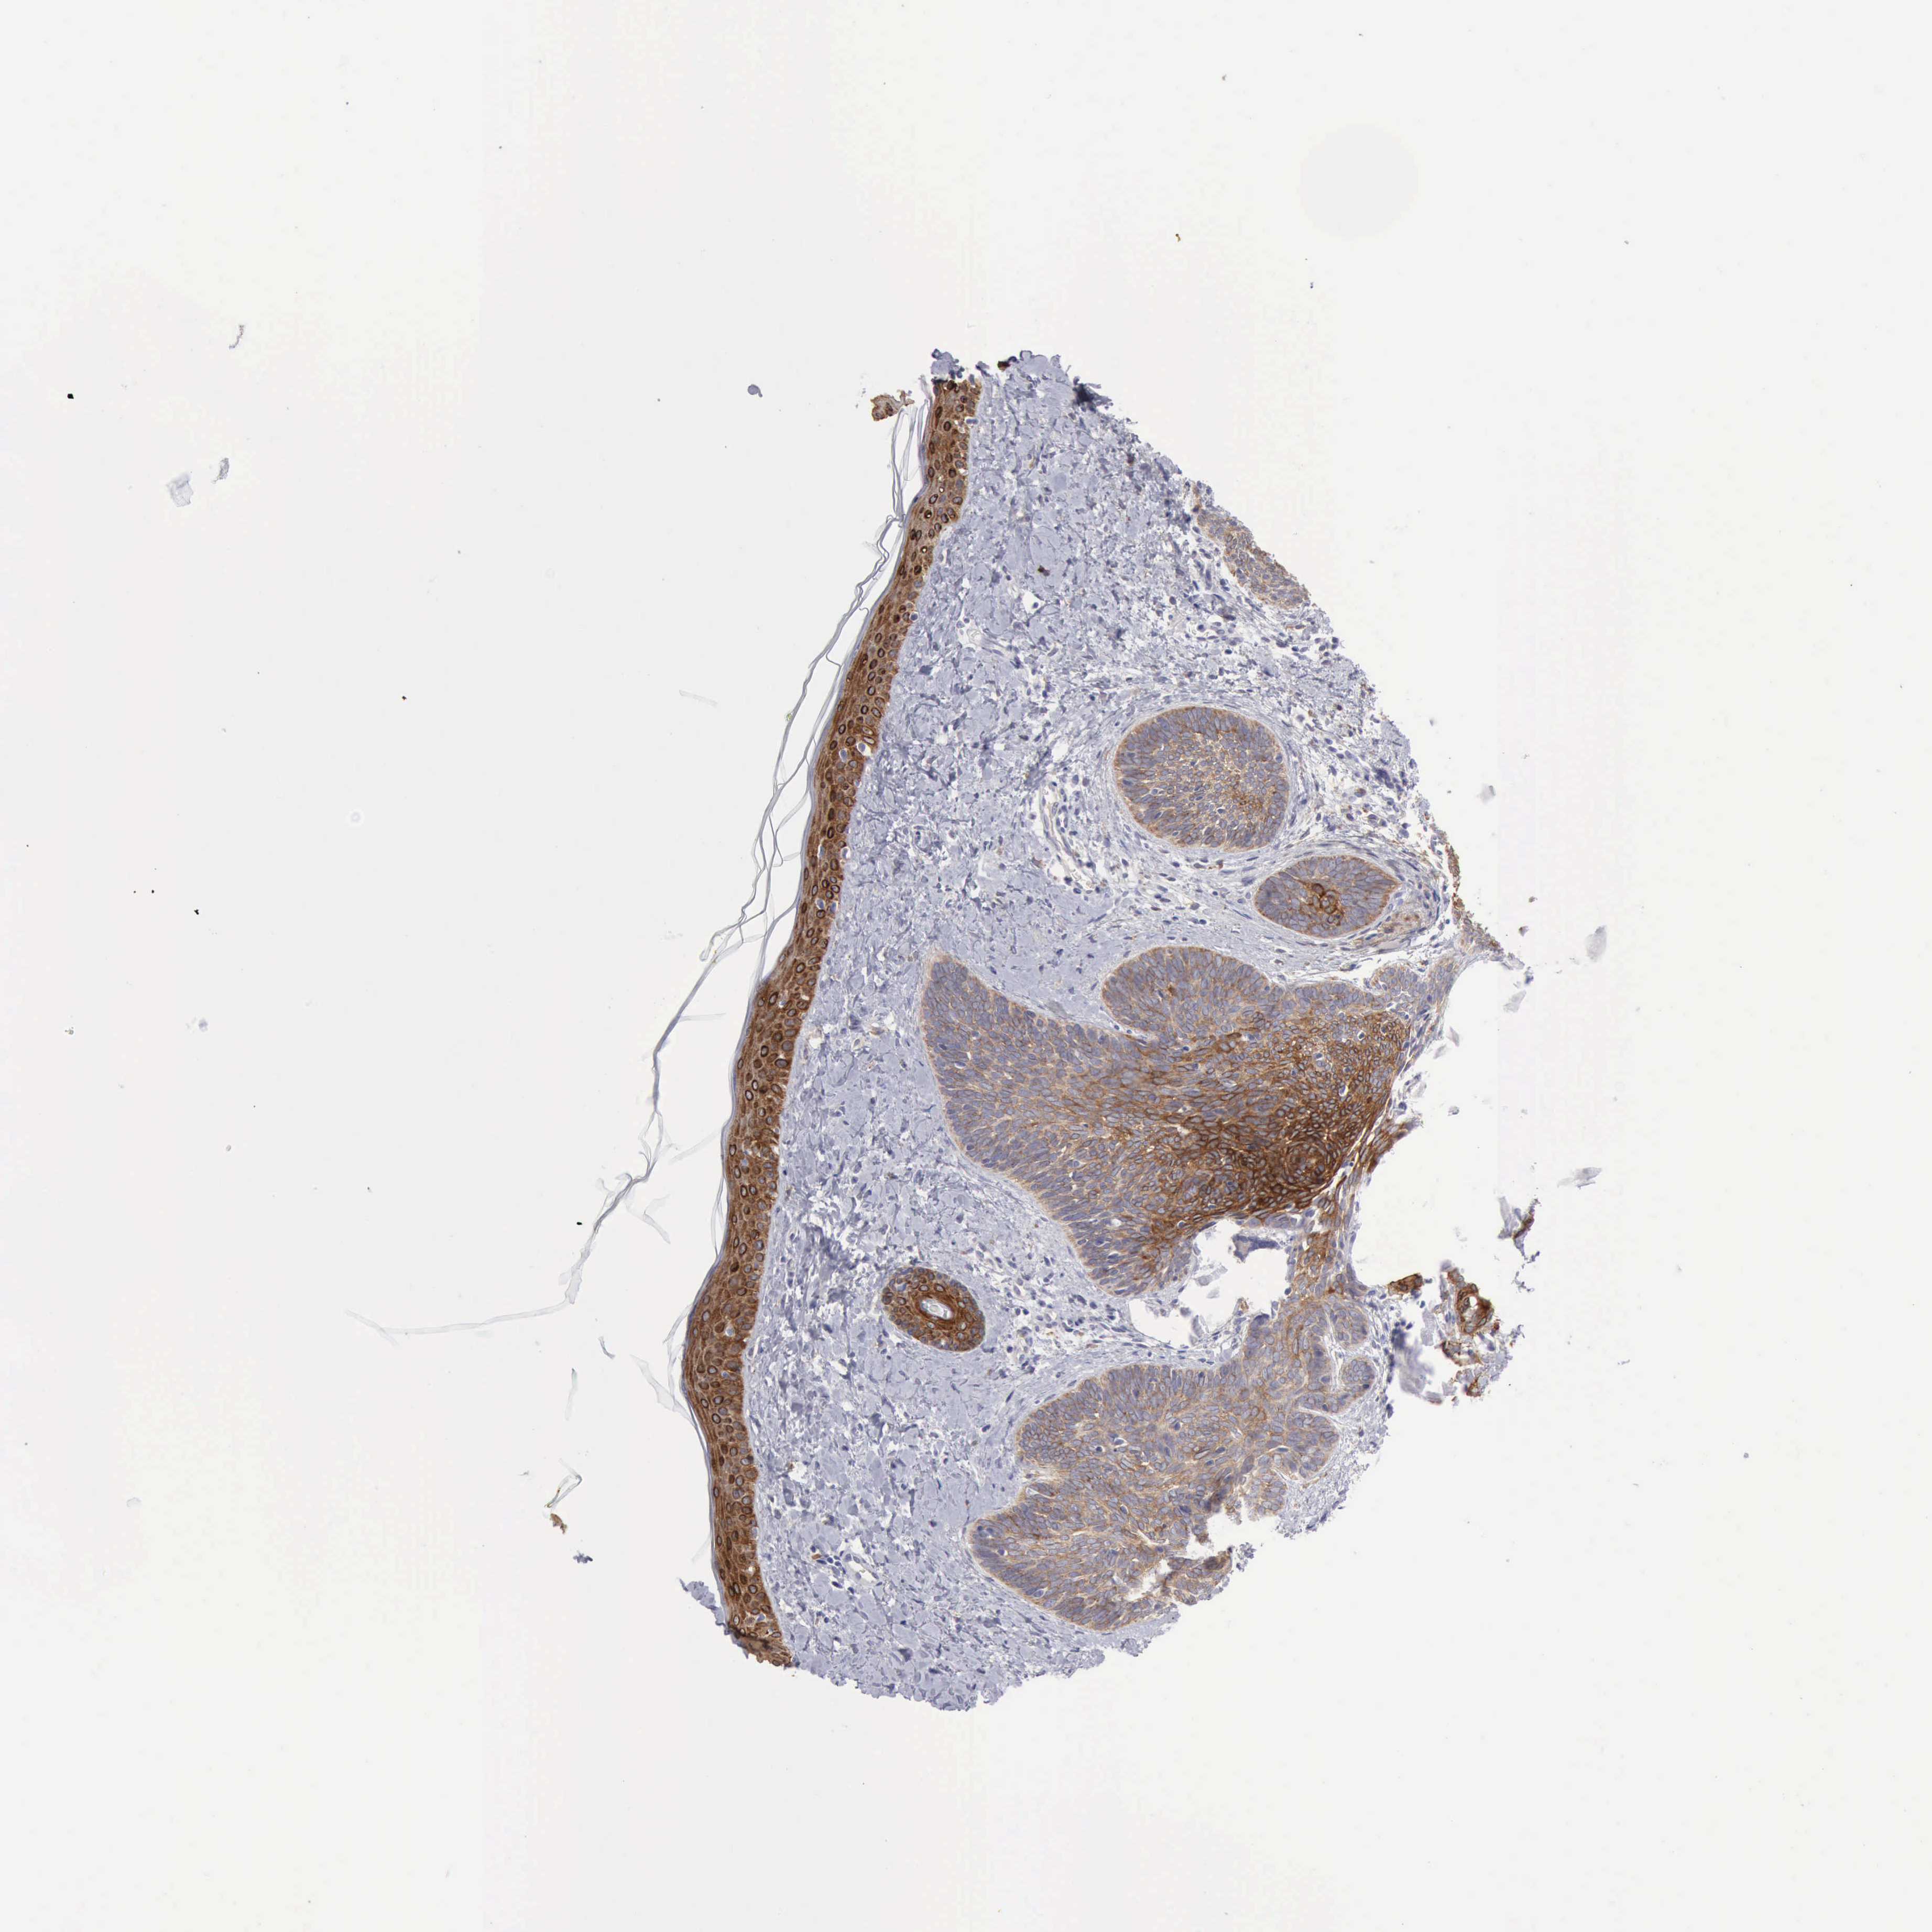

Basal cell and squamous cell cancer

SKIN CANCER - Protein expressioni

A mouse-over function shows sample information and annotation data. Click on an image to view it in a full screen mode. Samples can be filtered based on level of antibody staining by selecting one or several of the following categories: high, medium, low and not detected. The assay and annotation is described here.

Antibody stainingi

Antibody staining in the annotated cell types in the current human tissue is reported as not detected, low, medium, or high, based on conventional immunohistochemistry profiling in selected tissues. This score is based on the combination of the staining intensity and fraction of stained cells.

Each image is clickable and will lead to virtual microscopy that enables deeper exploration of all samples and also displays staining intensity scores, fraction scores and subcellular localization as well as patient and tissue information for each sample.

Antibody HPA028598

Basal cell carcinoma